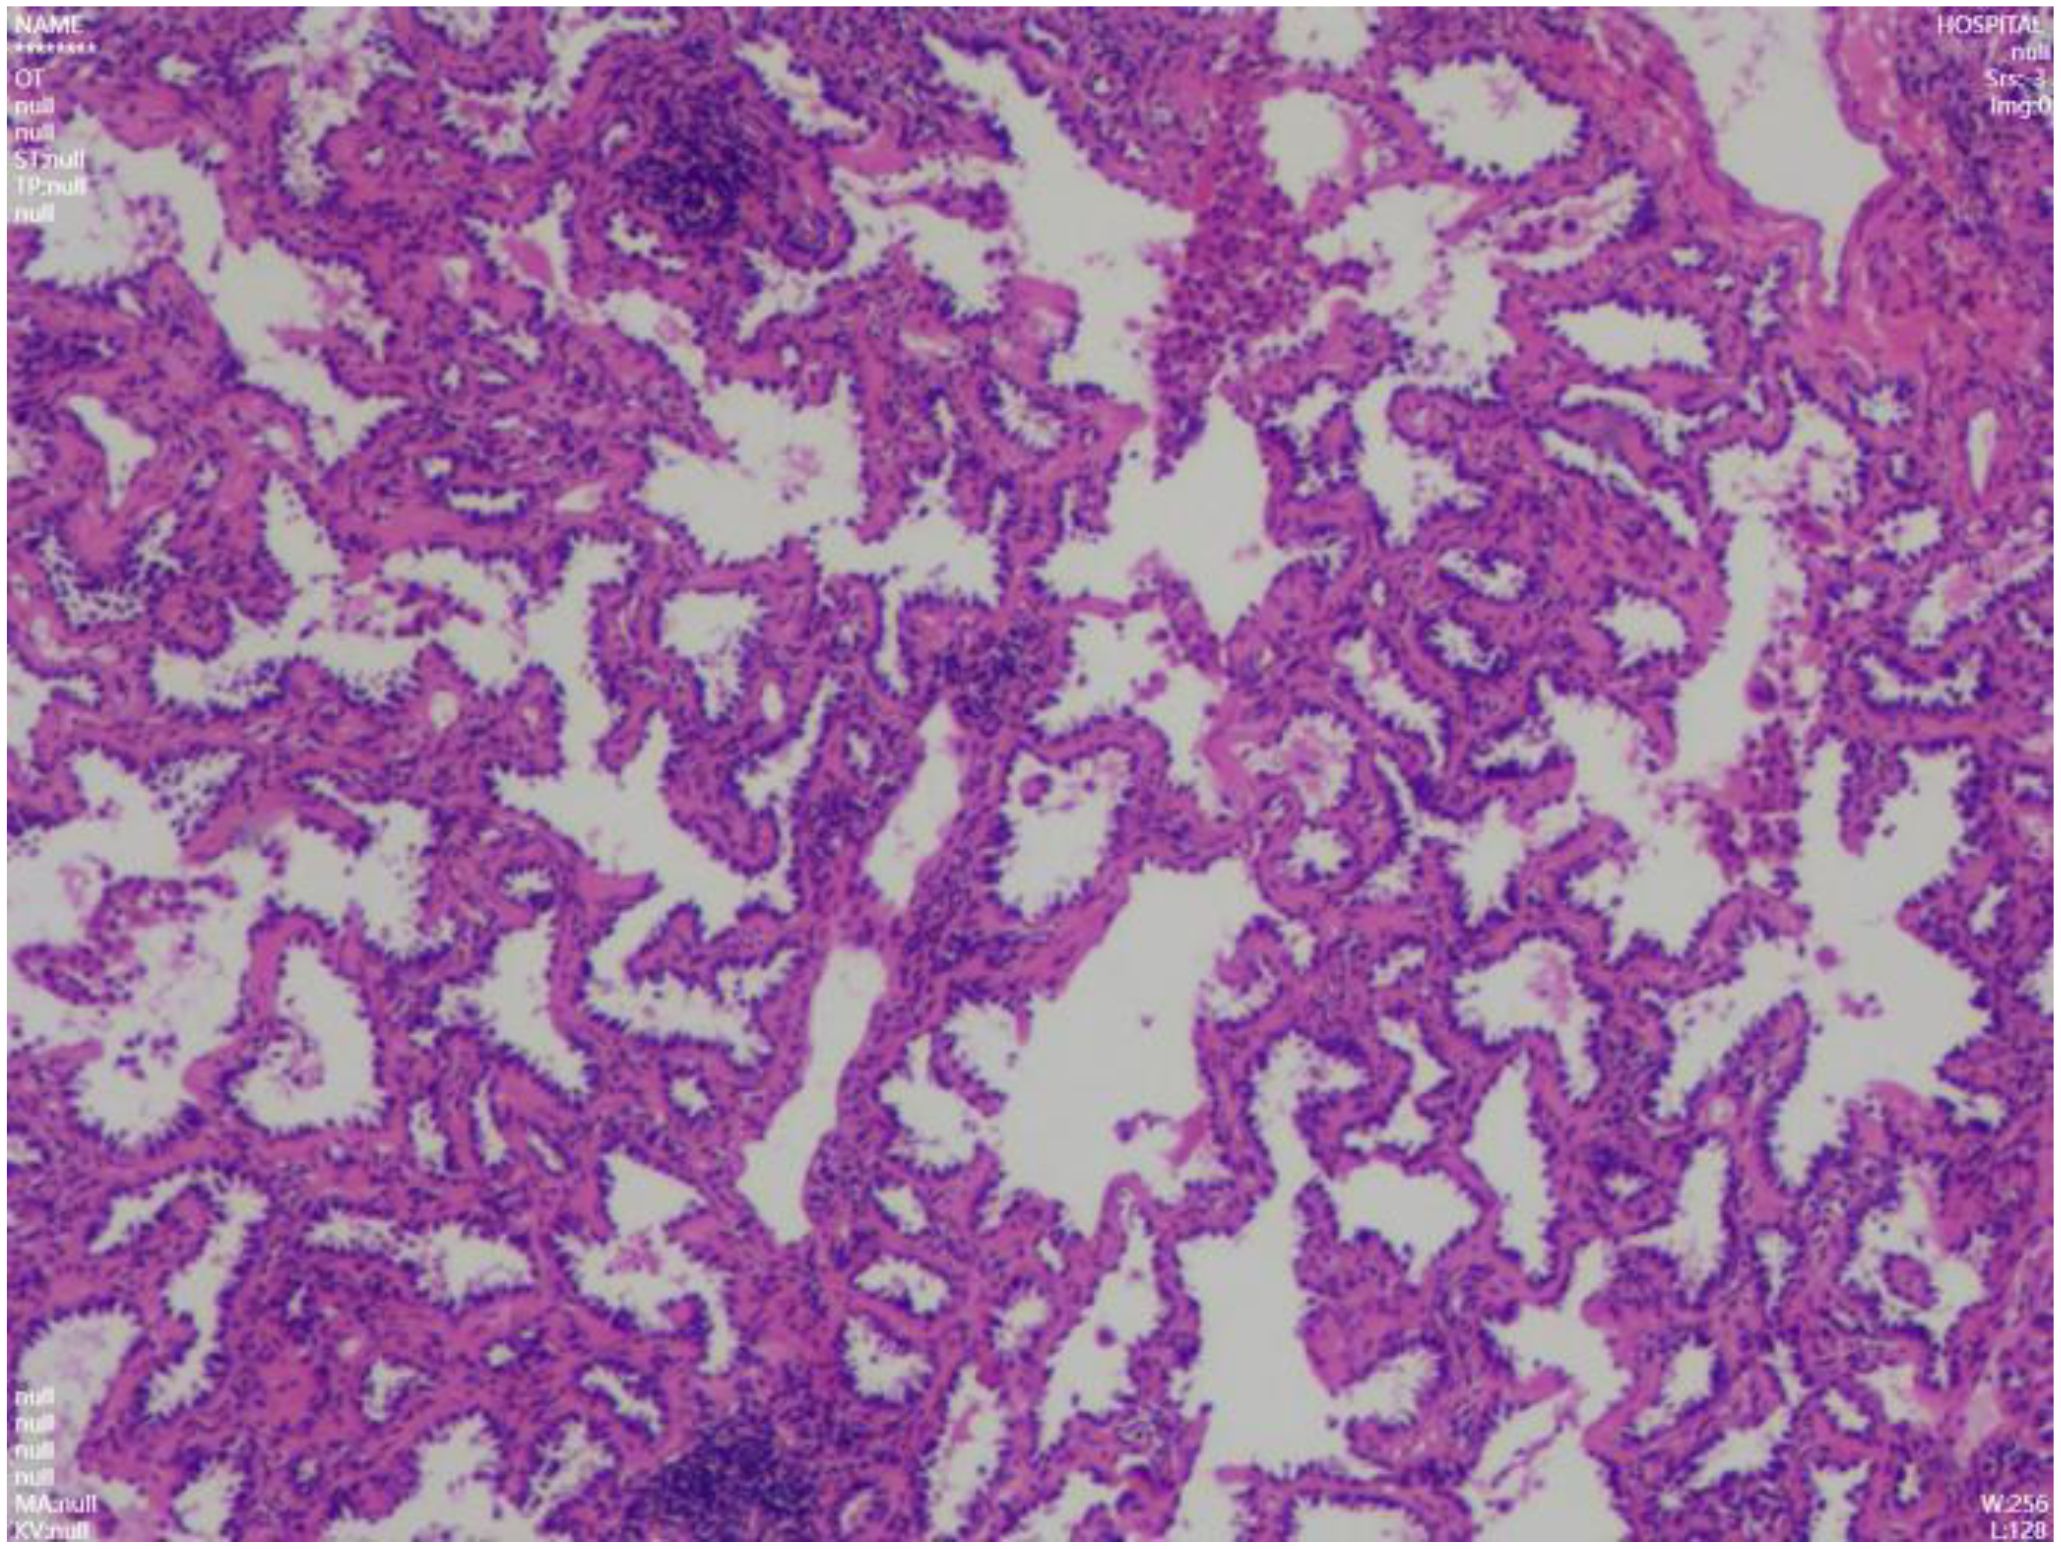

With the widespread use of plain chest CT scans, the detection of early-stage lung cancer has risen. This manuscript reviews surgical strategies for young patients with early-stage ground-glass nodules (GGNs) indicative of lung adenocarcinoma (LUAD), based on a case study and literature review, aiming to provide clinical insights for management. A 15-year-old adolescent male patient who underwent a routine chest CT, which revealed a ~0.7 cm GGN in the right upper lung. A follow-up CT on April 20, 2025, showed interval growth to approximately 9 × 8 mm in the apical segment. On July 1, 2025, the patient underwent wedge resection of the right upper lung via VATS. Postoperative pathology confirmed minimally invasive LUAD. The patient recovered well and was discharged the following day. A review of literature (2020–2025) identified seven cases of lung cancer in patients ≤18 years. Two patients did not undergo operation due to advanced disease. The remaining underwent surgical resection, with two requiring adjuvant therapy. In summary, lung cancer should be considered in the differential diagnosis of pulmonary nodules detected on plain chest CT. The decreasing age of onset underscores the need for timely intervention to prevent delayed treatment and improve prognosis.